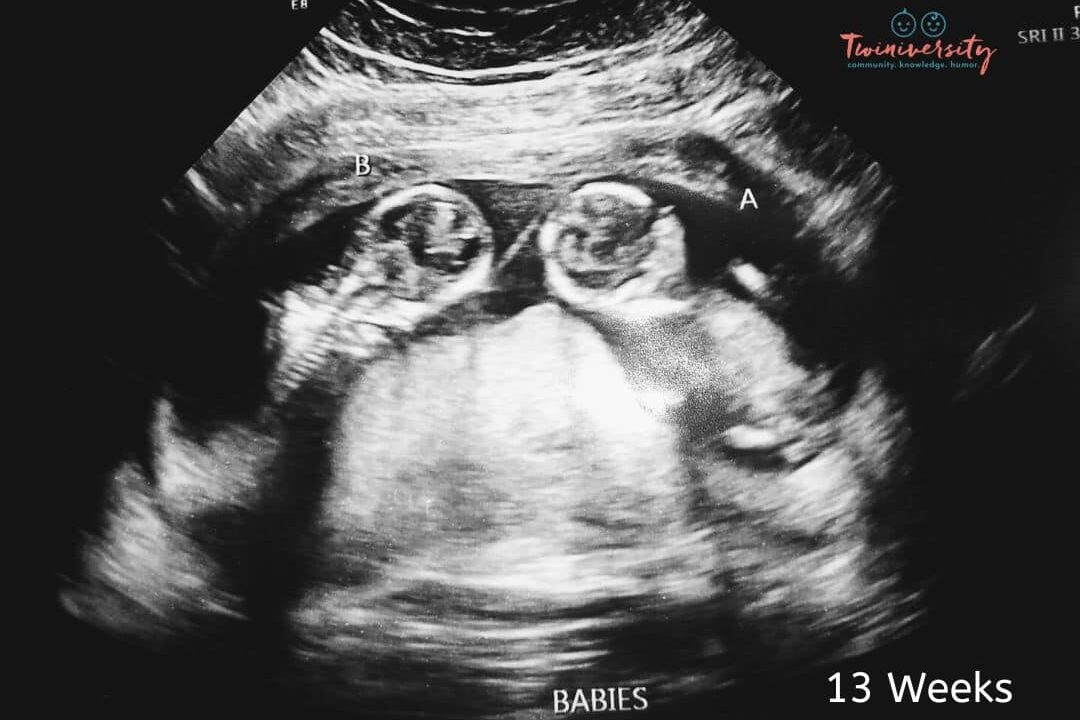

Imagine going for your 20-week ultrasound (halfway into your pregnancy), so excited to see your baby, and finding out that your baby is actually BABIES? It doesn’t happen super often, but sometimes a second baby goes undetected in early pregnancy. Most pregnant women find out its twins at their 8-week ultrasound, or even earlier. But see what twin moms had to say about finding out it was twins at a later ultrasound!

Let’s put it this way, nothing is truly impossible. It is highly unlikely that twins might go undetected. But, as you can see, it is certainly possible that you might have another little surprise in there and find out at a later ultrasound.

Again, it’s rare but possible to experience a “hidden twin” during your pregnancy. Mostly, the imaging available nowadays will pick up a second baby pretty early on. But a twin can be overlooked, especially if your provider isn’t looking for a twin at first glance.

How Late Can Twins Be Detected?

Twins will almost always be detected by your 20th week. It is unlikely you will even have to wait that long, but it can (and has) happened to many twin moms in our community. Beyond the 20 week mark, it is incredibly unlikely. But if you feel you are bigger than you should be or that something isn’t quite what you expected during your pregnancy, bring it up to your doctor.

Twins can typically be detected on ultrasound during the first trimester, usually around 6 to 8 weeks of gestation. In some cases, healthcare providers may be able to identify the presence of twins even earlier, especially with advanced ultrasound technology. The ability to visualize twins on an ultrasound depends on factors such as the clarity of the image, the position of the embryos, and the experience of the ultrasound technician.